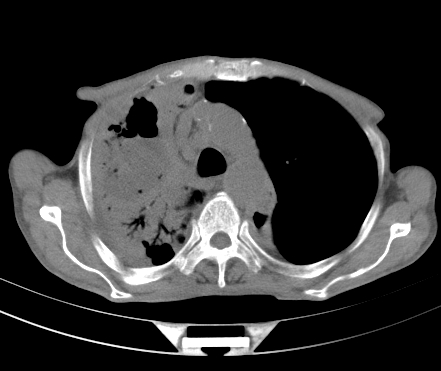

以下是引用gaoshengjiang在2008-5-30 19:53:00的发言:[br]右上叶可见大片实变影,其内可见充气支气管影及囊状影,右上叶尖端支气管走形区可见结节样影,左侧胸腔内可见胸腔胃影。纵隔淋巴结肿大。[br]考虑:1.右上肺阻塞性肺炎伴肺脓肿形成。支持转移所致。[br] 2.左侧胸腔胃。